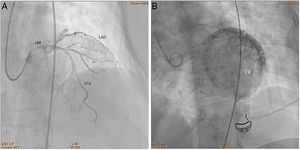

On admission, she presented with cardiogenic shock. Cardiac catheterization showed a dubious image of left main coronary artery dissection, without atherosclerotic lesions. An extremely slow flow in the left anterior descending and left circumflex arteries was noted (Figure 2A, Clip 1A), concomitant with contrast retention in the myocardial microcirculation (Figure 2B, Clip 1B).

A/Clip 1A. Cardiac catheterization. Left heart catheterization showing slow flow in the left main coronary artery and its branches. B/Clip 1B. Cardiac catheterization. Left heart catheterization showing myocardial microcirculation contrast retention. LAD: left anterior descending coronary artery; LCx: left circumflex coronary artery; LM: left main coronary artery; LV: left ventricle.